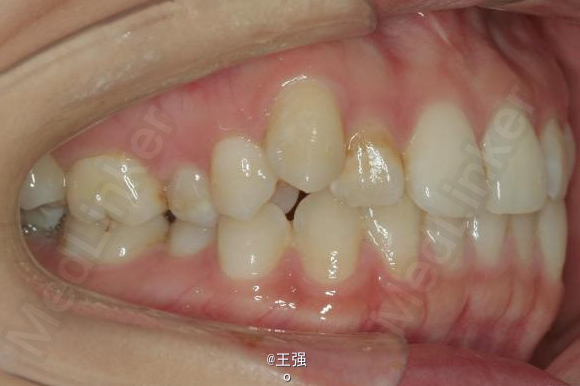

又一例不对称拔牙

牙弓狭窄,牙列拥挤

不对称拔牙